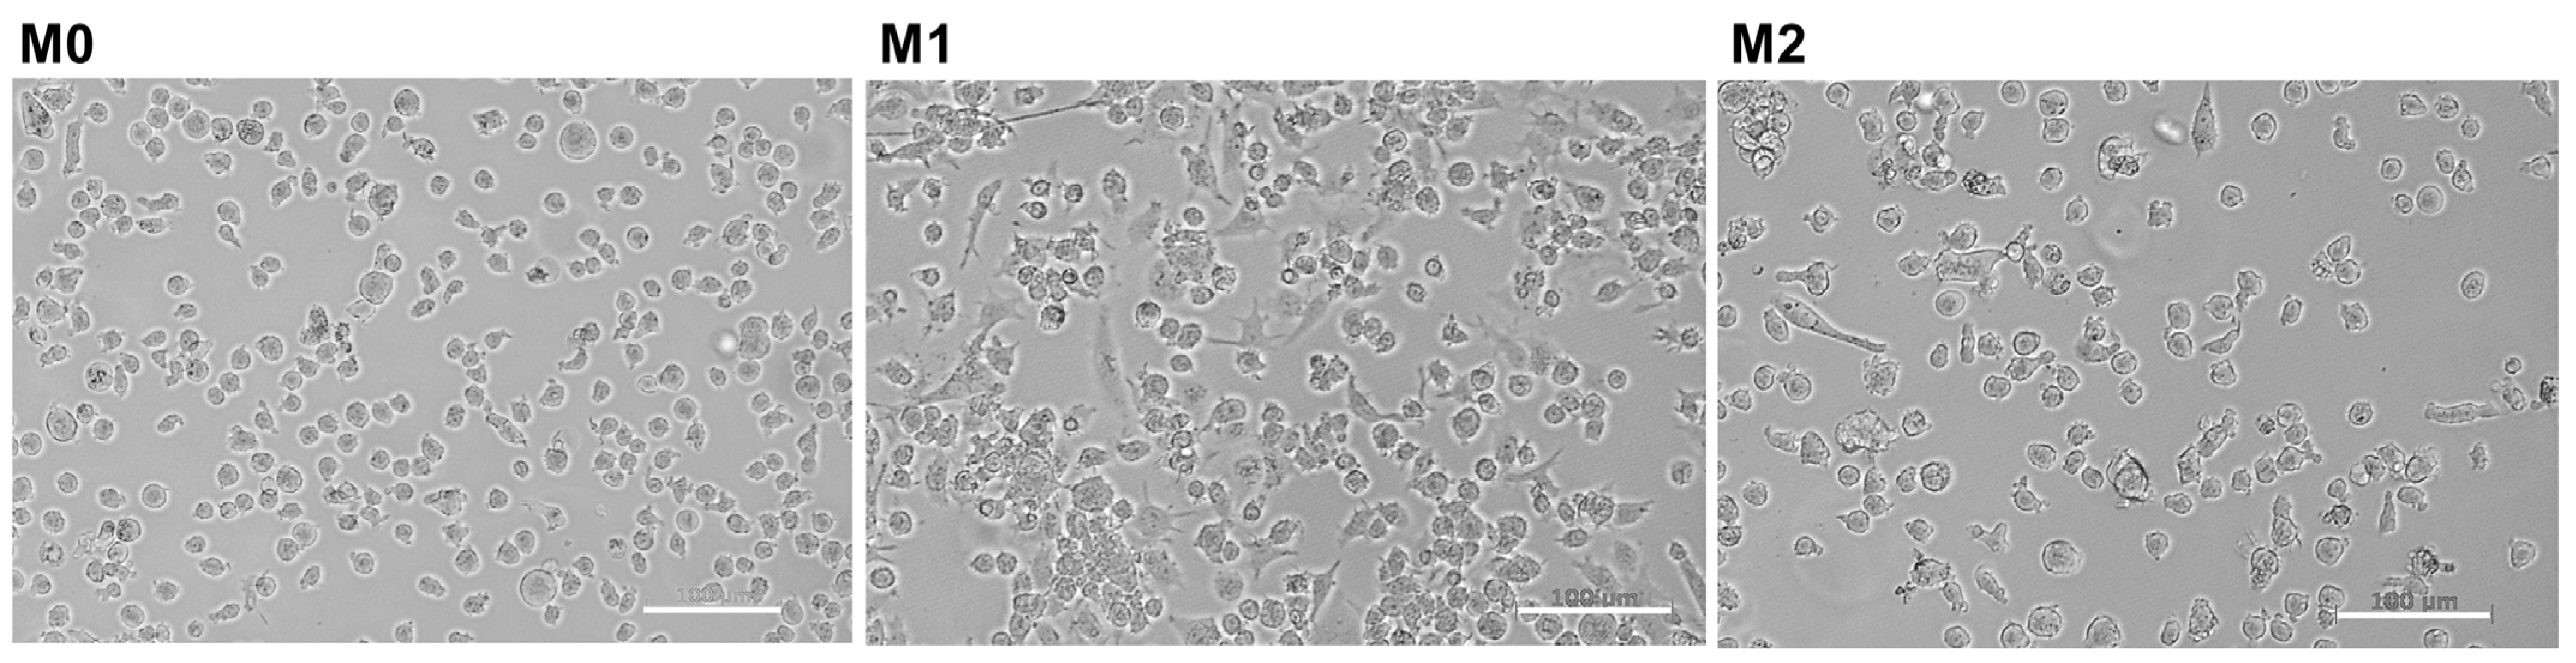

2.1. Induction of THP-1 Differentiation and Polarization